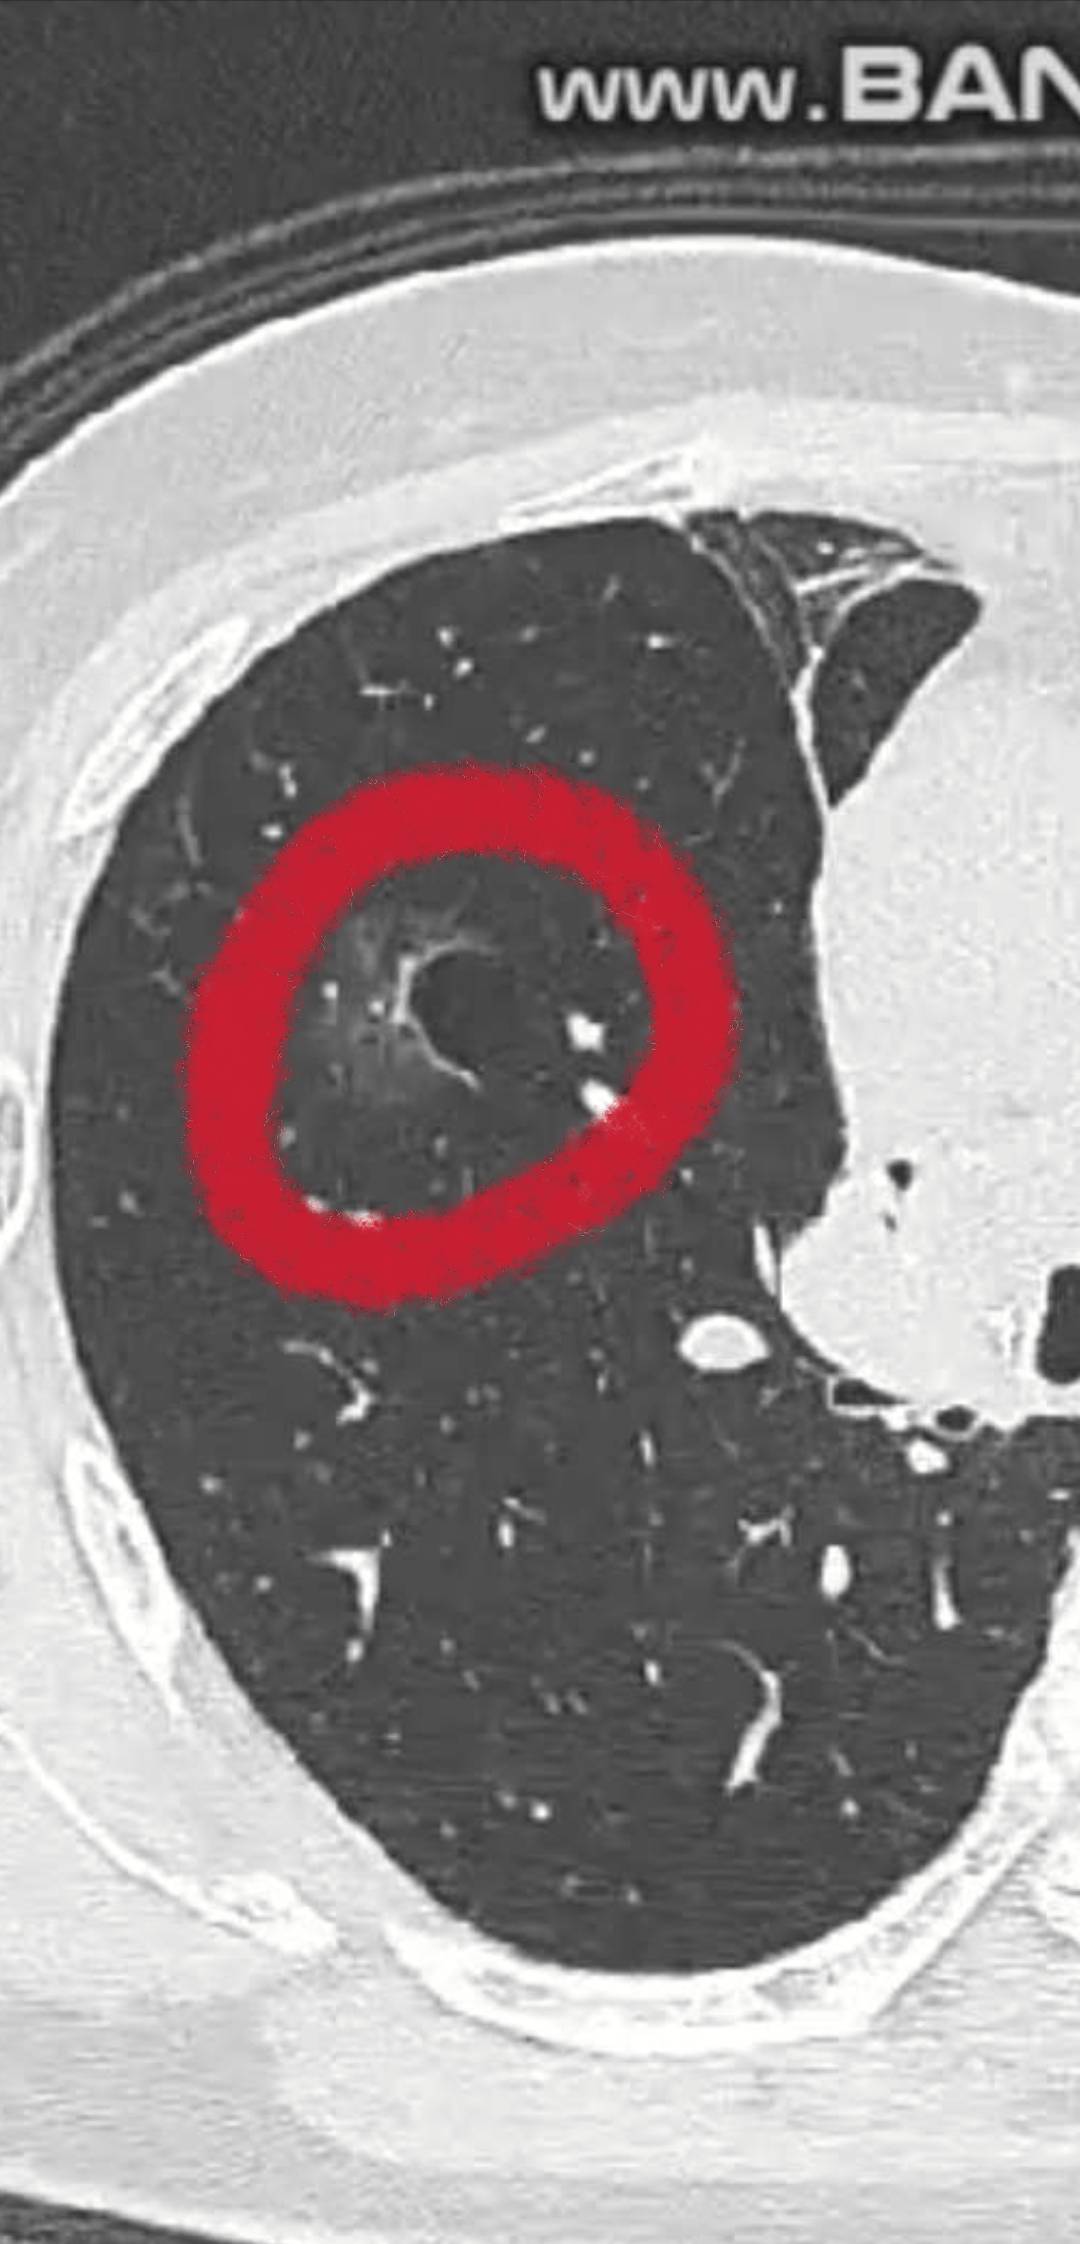

多发磨玻璃结节,降期后的结节,可以考虑消融"烧掉",但这种结节风险就很大

病情如图,总结起来就是相互独立的多发的磨玻璃结节,最大的切掉了。后续的"种子",又陆续长大。陈医生看了文字咨询,本来想建议消融烧掉的,但看了图后,却觉得不是很好烧了。因为结节长在一个气泡周边,可能会把气泡烧到,造成"漏气"